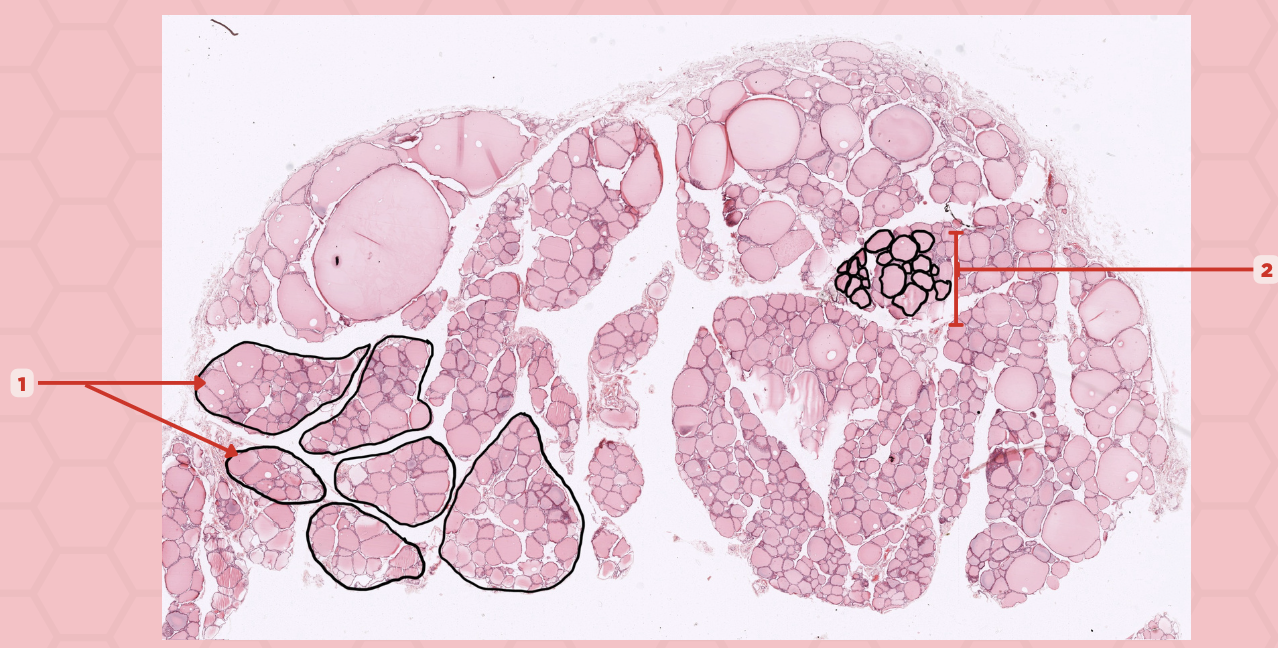

Thyroid

Identify the specimen.

Lobules

Identify the structure labeled as 1.

Follicles

Identify the structure labeled as 2.